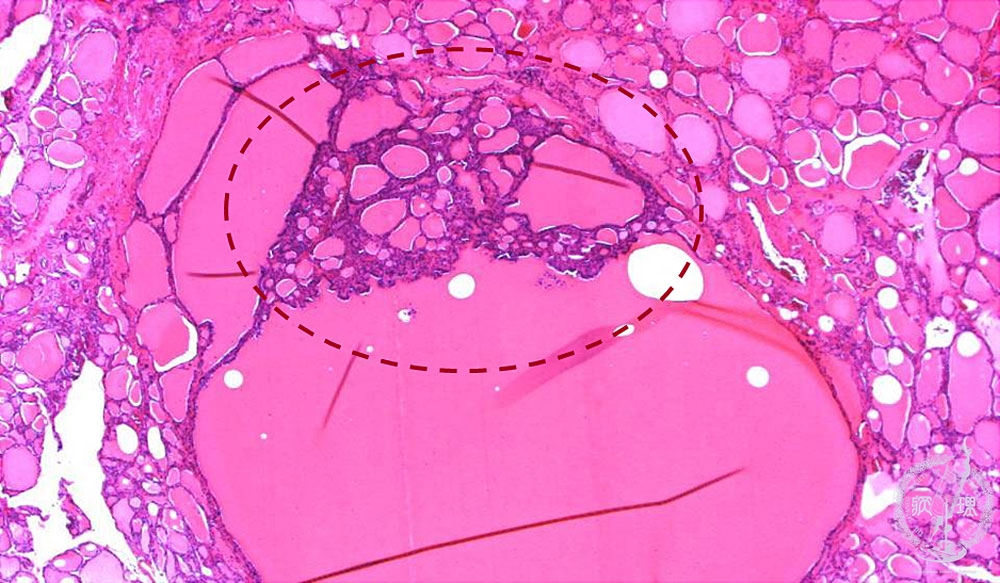

- (6)Nodular (adenomatous) goiter

Microscopic findings (HE stain, low power view): Projection of small follicles into large follicular space (dotted -line), also called “Sanderson polster”, is characteristic of nodular goiter.